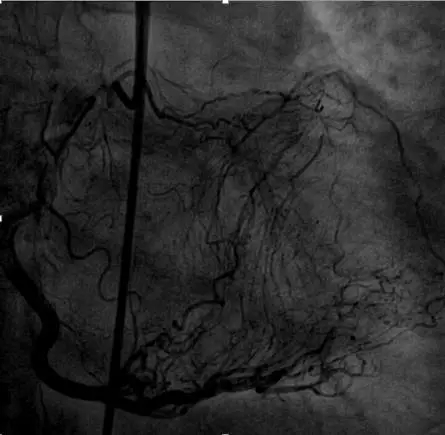

左冠PCI

Culotte技术

LAD—Resolute 3.0*30mm

LM-LCX—Resolute 3.0*30mm

LM-LAD—+Resolute 3.5*30mm

LCX开口狭窄

Finecross及双腔微导管支持下,

导丝均无法穿LM-LAD支架网眼至LCX

再次逆向掏LCX网眼

穿微导管技术( Modified Rendezvous )

球囊对吻、后扩张

POT

IVUS结果